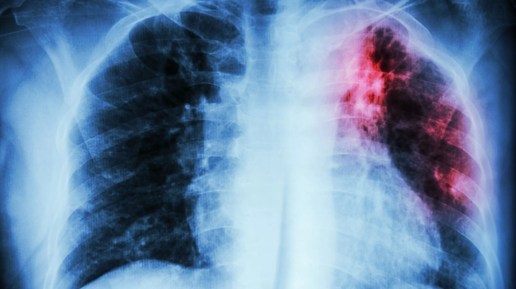

🎁 Гайд "Лабораторная диагностика туберкулеза" из нашего нового курса по микробиологии

🎁 Гайд "Лабораторная диагностика туберкулеза" из нашего нового курса по микробиологии. Приготовили вам такой вот подарочек в честь запуска курса. Да, мы наконец-то его отсняли, успели к сентябрю, чтобы у вас все было...